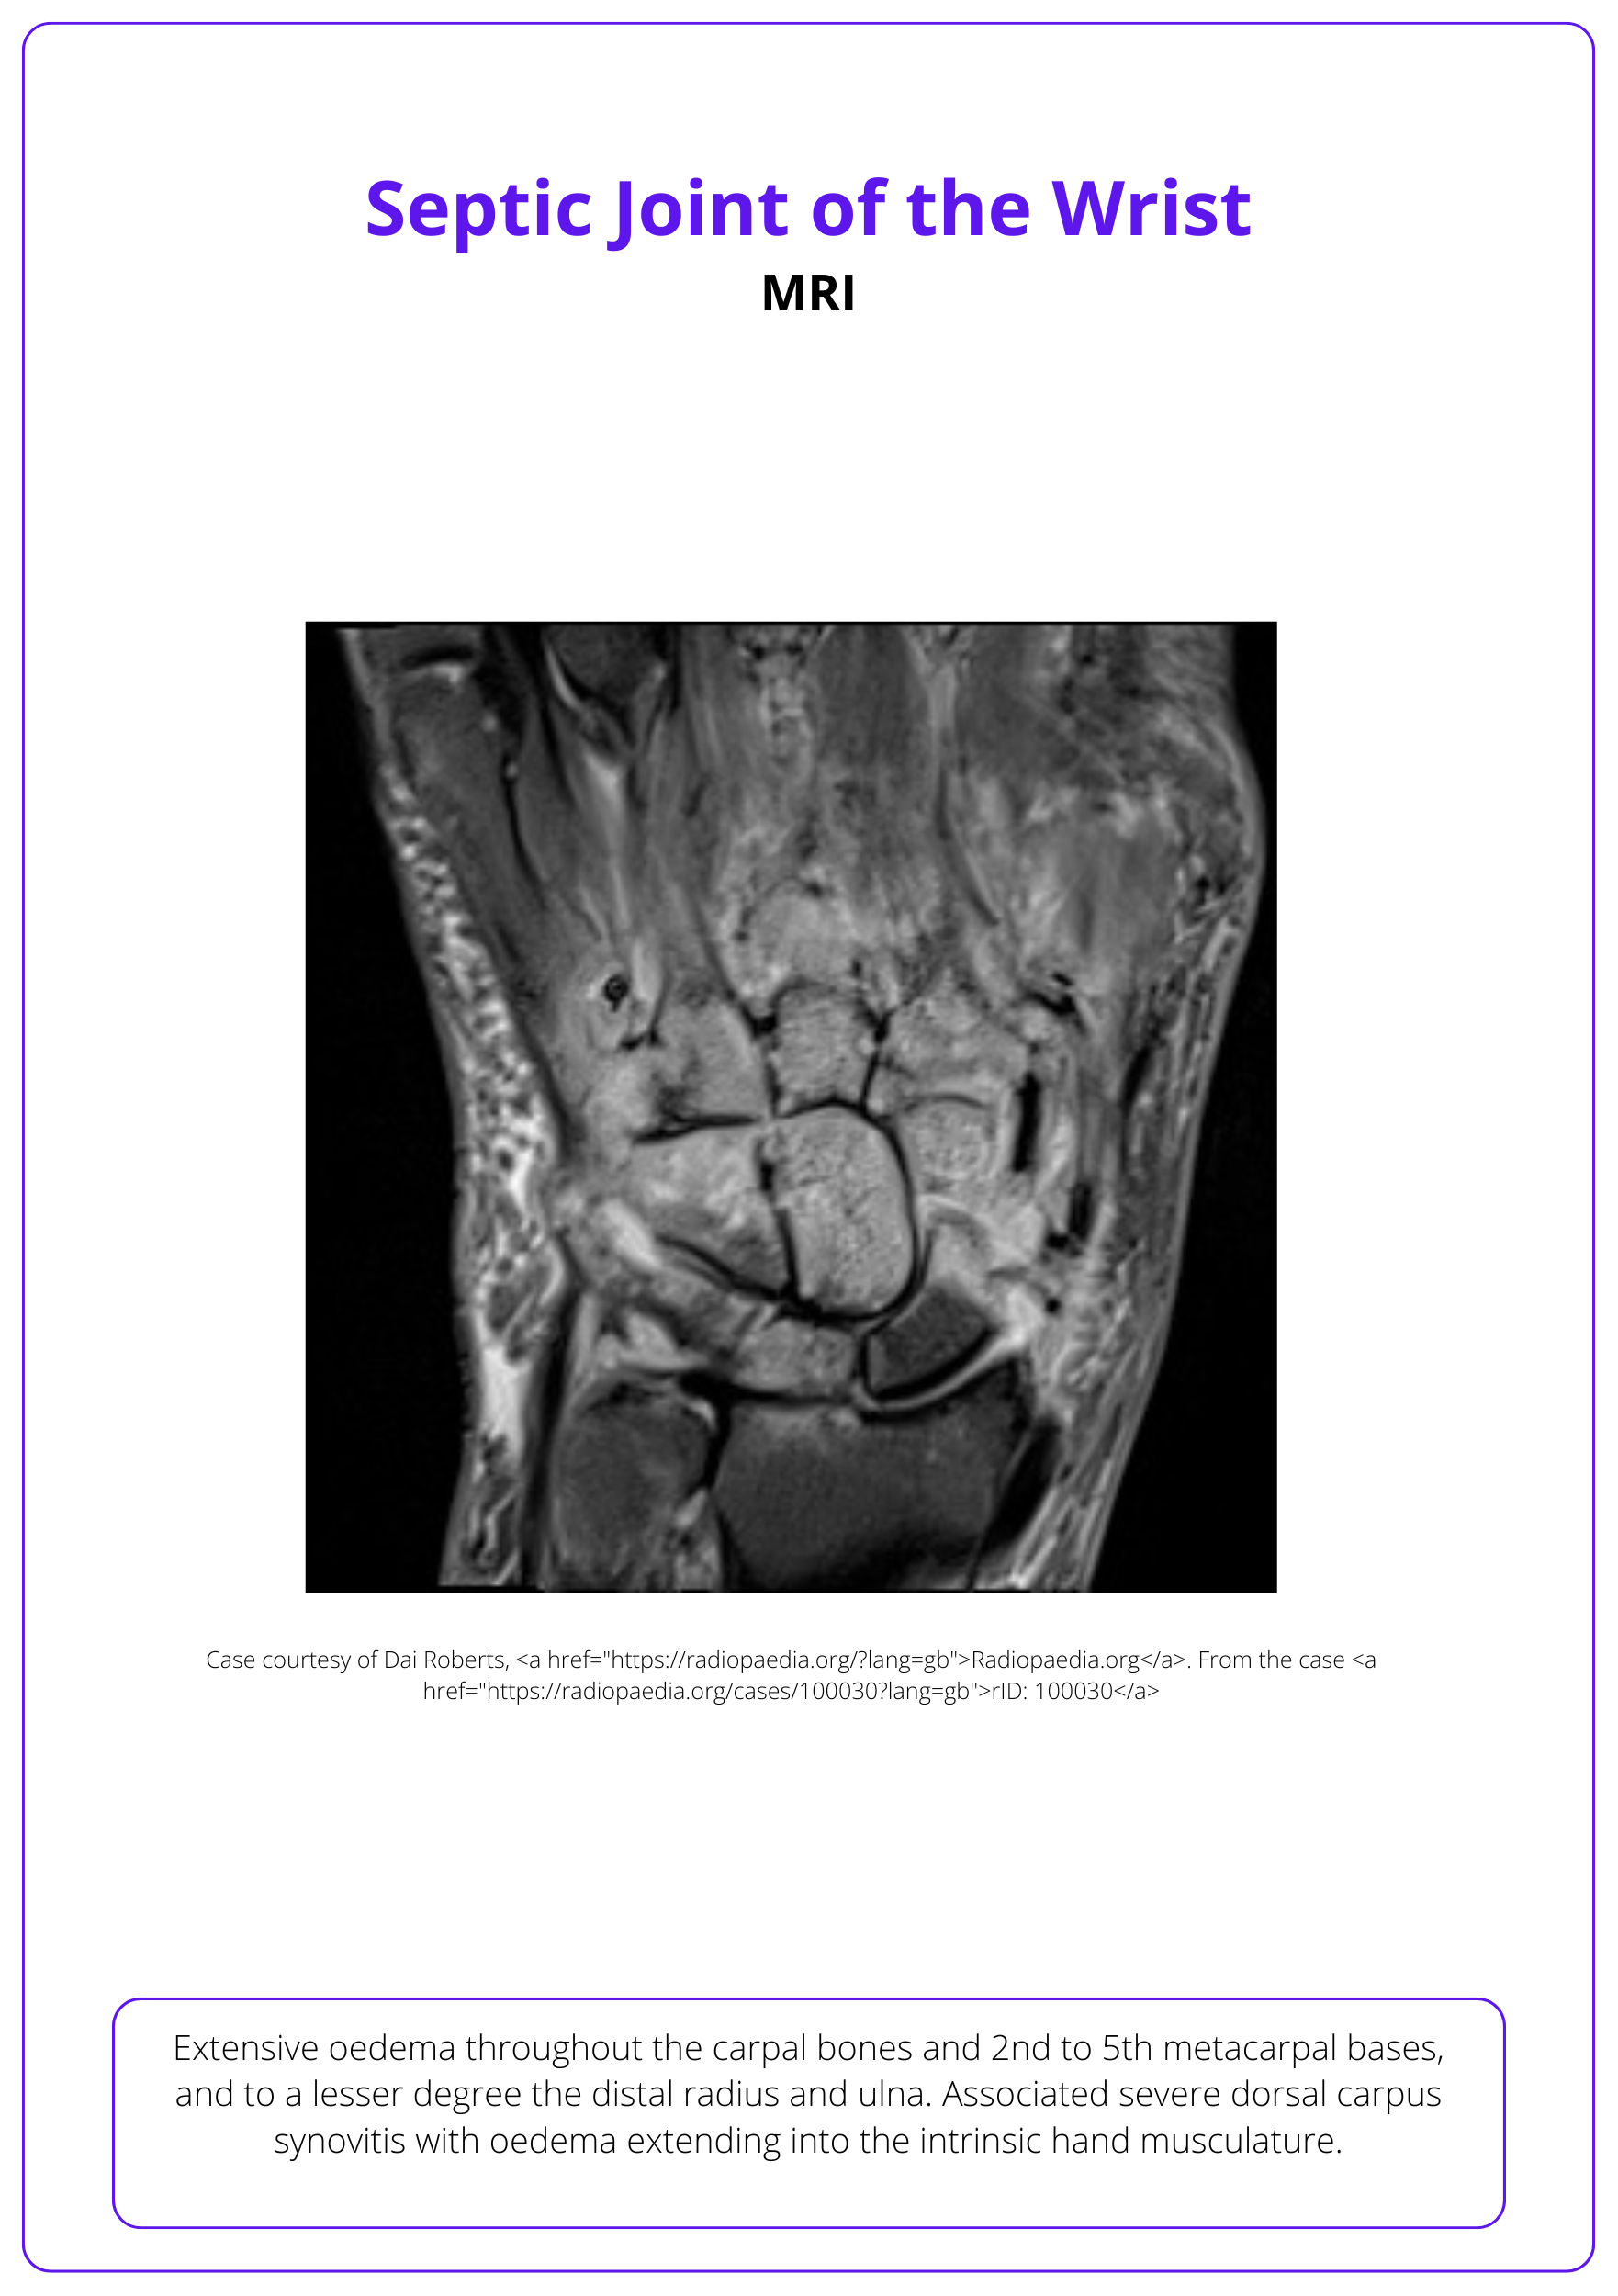

- Septic Arthritis: Main Article and Clinical Case